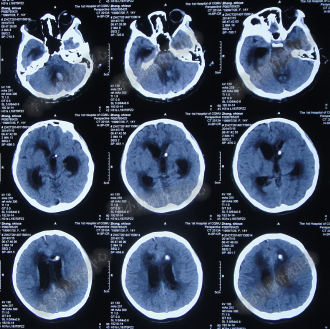

2014年8月31日住入李小勇脑脊液中心,入院时:卧床,表情淡漠,神志嗜睡;体温高37.9°C;头颅枕后正中手术瘢痕,结痂尚未脱落;左枕侧脑室外引流固定在位,尚通畅,可见淡红色浑浊脑脊液引出;颈抵抗,双肺呼吸音粗(图-27);头部CT检查示(小脑肿瘤术后颅内感染病例)脑室系统粘连严重伴双侧颞角脑室扩张明显,双侧侧脑室见引流管影,脑内见多发斑片低密度,中线结构无移位,颅骨术后改变(图-28)。

图-27:2014年8月31日入院时

图-28:2014年8月31日头部CT